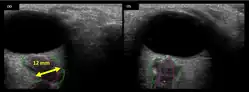

The astronauts affected by long term visual changes and prolonged intracranial hypertension have all been male, and SOS may explain this because in men, the sternocleidomastoid muscle is typically thicker than in women and may contribute to more compression. The reason that SOS does not occur in all individuals may be related to anatomic variations in the internal jugular vein. Ultrasound study has shown that in some individuals, the internal jugular vein is located in a more lateral position to Zone I compression, and therefore not as much compression will occur, allowing continued blood flow.

The first U.S. case of visual changes observed on orbit was reported by a long-duration astronaut that noticed a marked decrease in near-visual acuity throughout his mission on board the ISS, but at no time reported headaches, transient visual obscurations, pulsatile tinnitus or diplopia (double vision). His postflight fundus examination (Figure 1) revealed choroidal folds below the optic disc and a single cotton-wool spot in the inferior arcade of the right eye. The acquired choroidal folds gradually improved, but were still present 3 year postflight. The left eye examination was normal. There was no documented evidence of optic-disc edema in either eye. Brain MRI, lumbar puncture, and OCT were not performed preflight or postflight on this astronaut.[5]

The sixth case of visual changes of an ISS astronaut was reported after return to Earth from a 6-month mission. When he noticed that his far vision was clearer through his reading glasses. A fundus examination performed 3 weeks postflight documented a grade 1 nasal optic-disc edema in the right eye only. There was no evidence of disc edema in the left eye or choroidal folds in either eye (Figure 13). MRI of the brain and eyes days postflight revealed bilateral flattening of the posterior globe, right greater than left, and a mildly distended right optic nerve sheath. There was also evidence of optic-disc edema in the right eye. A fundus examination postflight revealed a "new onset" cotton-wool spot in the left eye. This was not observed in the fundus photographs taken 3 weeks postflight.[5]

The seventh case of visual changes associated with spaceflight is significant in that it was eventually treated postflight. Approximately 2 months into the ISS mission, the astronaut reported a progressive decrease in his near and far acuity in both eyes. The ISS cabin pressure, CO2 and O2 levels were reported to be within normal operating limits and the astronaut was not exposed to any toxic substances. He never experienced losses in subjective best-corrected acuity, color vision or stereopsis. A fundus examination revealed a grade 1 bilateral optic-disc edema and choroidal folds (Figure 15).[5]